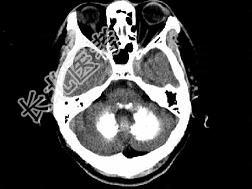

- 单项选择题男,49岁, 反复发作性癫痫,双手震颤5年, 伴头昏行走不稳,生化检查: 血清钙降低,血清磷升高, 请根据所提供图像,选择最可能的诊断 ( )

A、Fahr病

B、一氧化碳中毒性脑病

C、霉变甘蔗中毒

D、肝豆状核变性

E、甲旁低